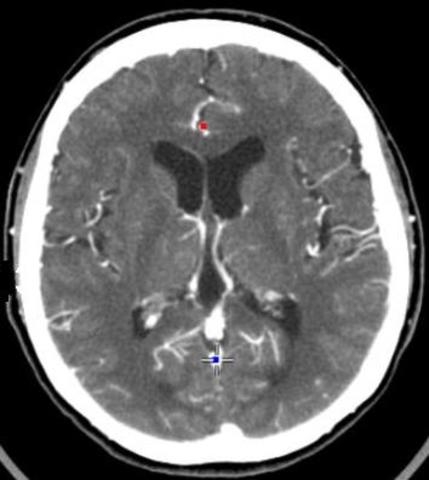

• Ct Scans

Ct Scans

CT scans (or CAT scans) are a series of x-ray images taken from different angles and scans the whole body and can kind of tell what is right and wrong with your body. CT scans are more detailed than the average x-ray. As you may know, CT scans are VERY expensive, they cost around $1,200. CT stands for Computerized Tomography.